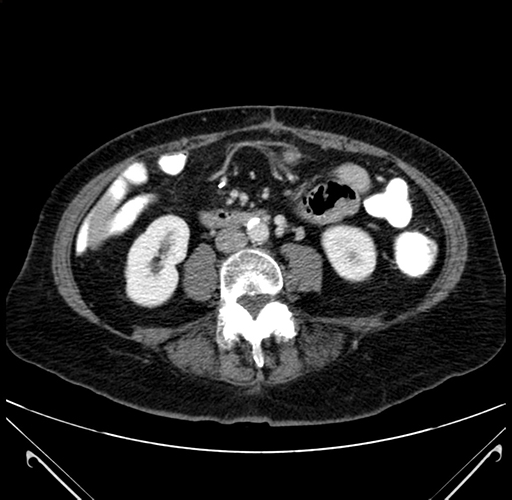

Pre-Chemo: Axial Venous

Axial Venous